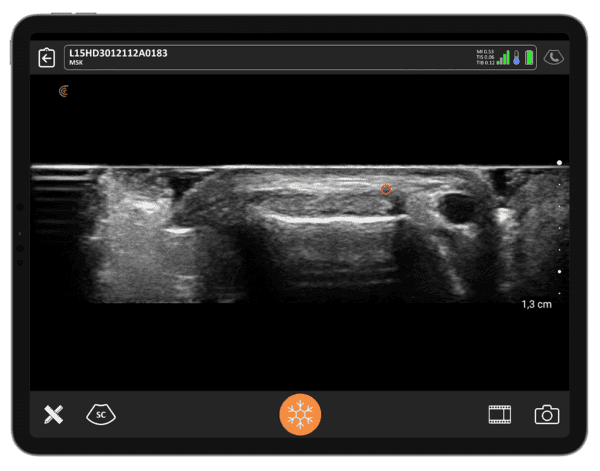

POCUS for MSK: Mastering Hand and Wrist Ultrasound

Join renowned SonoSkills founder and educator Mr. Marc Schmitz as he shares valuable POCUS tips, tricks, and best practices tailored for anyone with an interest in broadening their knowledge of hand and wrist ultrasound for common pathologies.

In this 1-hour webinar, you’ll learn wireless ultrasound techniques to improve your MSK scanning skills. With a focus on hand and wrist anatomy and pathophysiology of common conditions, expert sonographer Mr. Schmitz will teach:

- The ultrasound appearance of key structures in the wrist, hand & fingers

- Demonstrate proficiency in utilizing ultrasound for comprehensive wrist, hand & fingers musculoskeletal assessments

- How to apply knowledge of wrist, hand & fingers into clinical diagnostic practice

- Diagnostic ultrasound techniques to differentiate between various wrist, hand & fingers pathologies